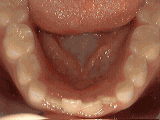

Non-braces treatment

Sometimes braces are not needed to get noticeable improvements in tooth alignment. This patient was first seen at age seven for crowding of the lower permanent teeth. A procedure was performed to reduce the width of the adjacent baby teeth and the permanent incisors aligned on their own in nine months.